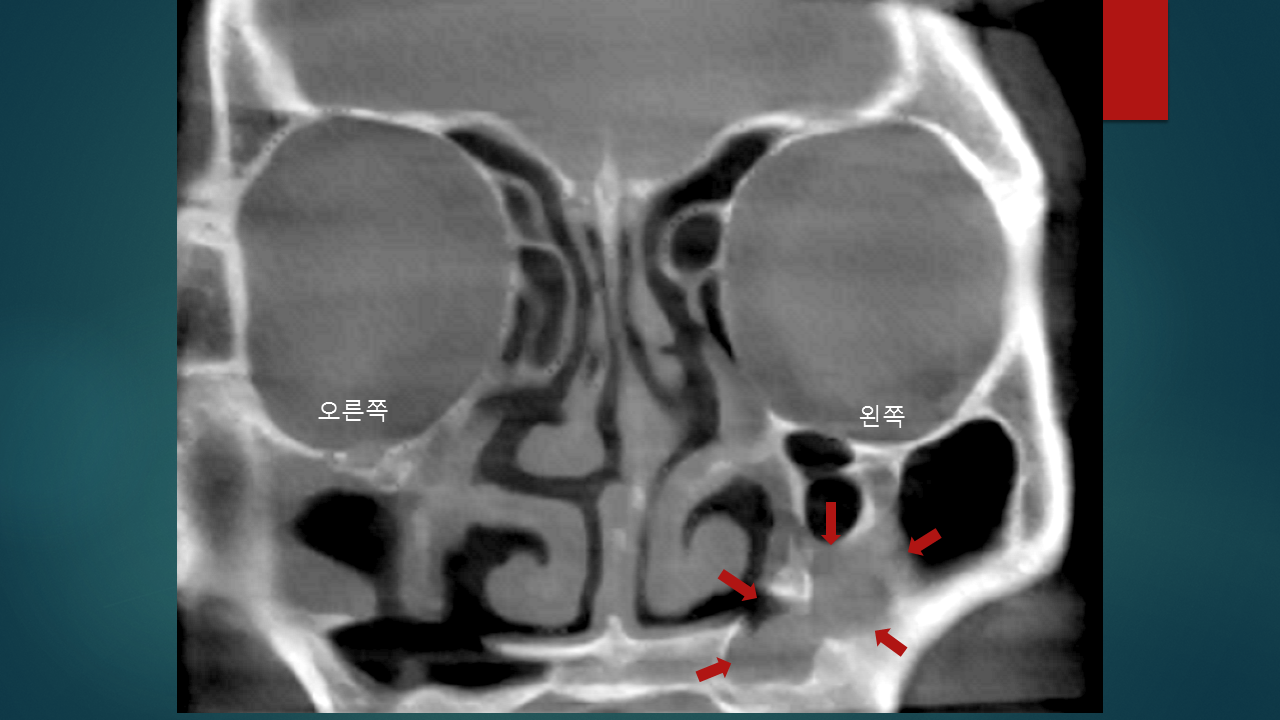

환자분은 대학병원에서 두번의 축농증 수술을 받으셨고, 세번째 재발하여 지난 1월에코리아이비인후과를 방문해주셨…